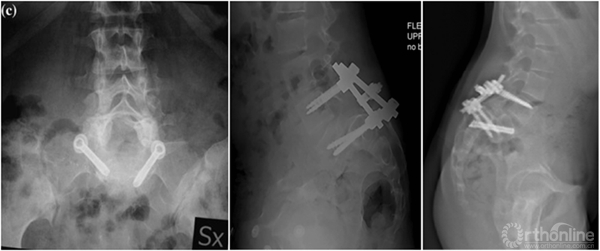

① 对于失平衡不重者,可以采取一期后路部分复位和经骶骨轴向融合方式[4]。

② 明显失平衡者,采取后路复位联合前路支撑重建术式。

① 采取前后联合,骶骨部分截骨、复位和椎间支撑重建手术[8]。

② 我们的病例